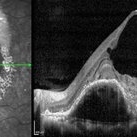

Polypoidal choroidal vasculopathy

Nov 21 2022 by T. P . VIGNESH, MBBS,MS

SD-OCT of a 60 year old woman revealing a large PED , multilobular PED and subretinal hemorrhage .

Photographer: Priyanka

Imaging device: Heidelberg Spectralis

Condition/keywords: polypoidal choroidal vasculopathy (PCV)